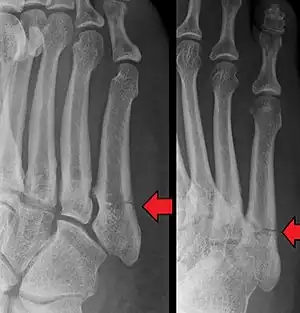

Differential diagnosis

- Proximal diaphysis, typically stress fracture.[15][16]

- Metaphysis: Jones fracture[17]

-Tuberosity: Pseudo-Jones fracture[18] (avulsion fracture).[18]

Other proximal fifth metatarsal fractures exist, although they are not the same as a Jones fracture; if the fracture enters the intermetatarsal joint, it is a Jones fracture[14]. If, however, it enters the tarsometatarsal joint, then it is an avulsion fracture caused by pull from the peroneus brevis.[21][22]

This injury should be differentiated from the developmental "apophysis" which is the secondary ossification center of the metatarsal bone, it is normally occurring at this site in adolescents. Differentiation is possible by characteristics such as absence of sclerosis of the fractured edges. It is transverse to the metatarsal axis for the fracture – and parallel to the metatarsal axis in the case of the apophysis.[23]